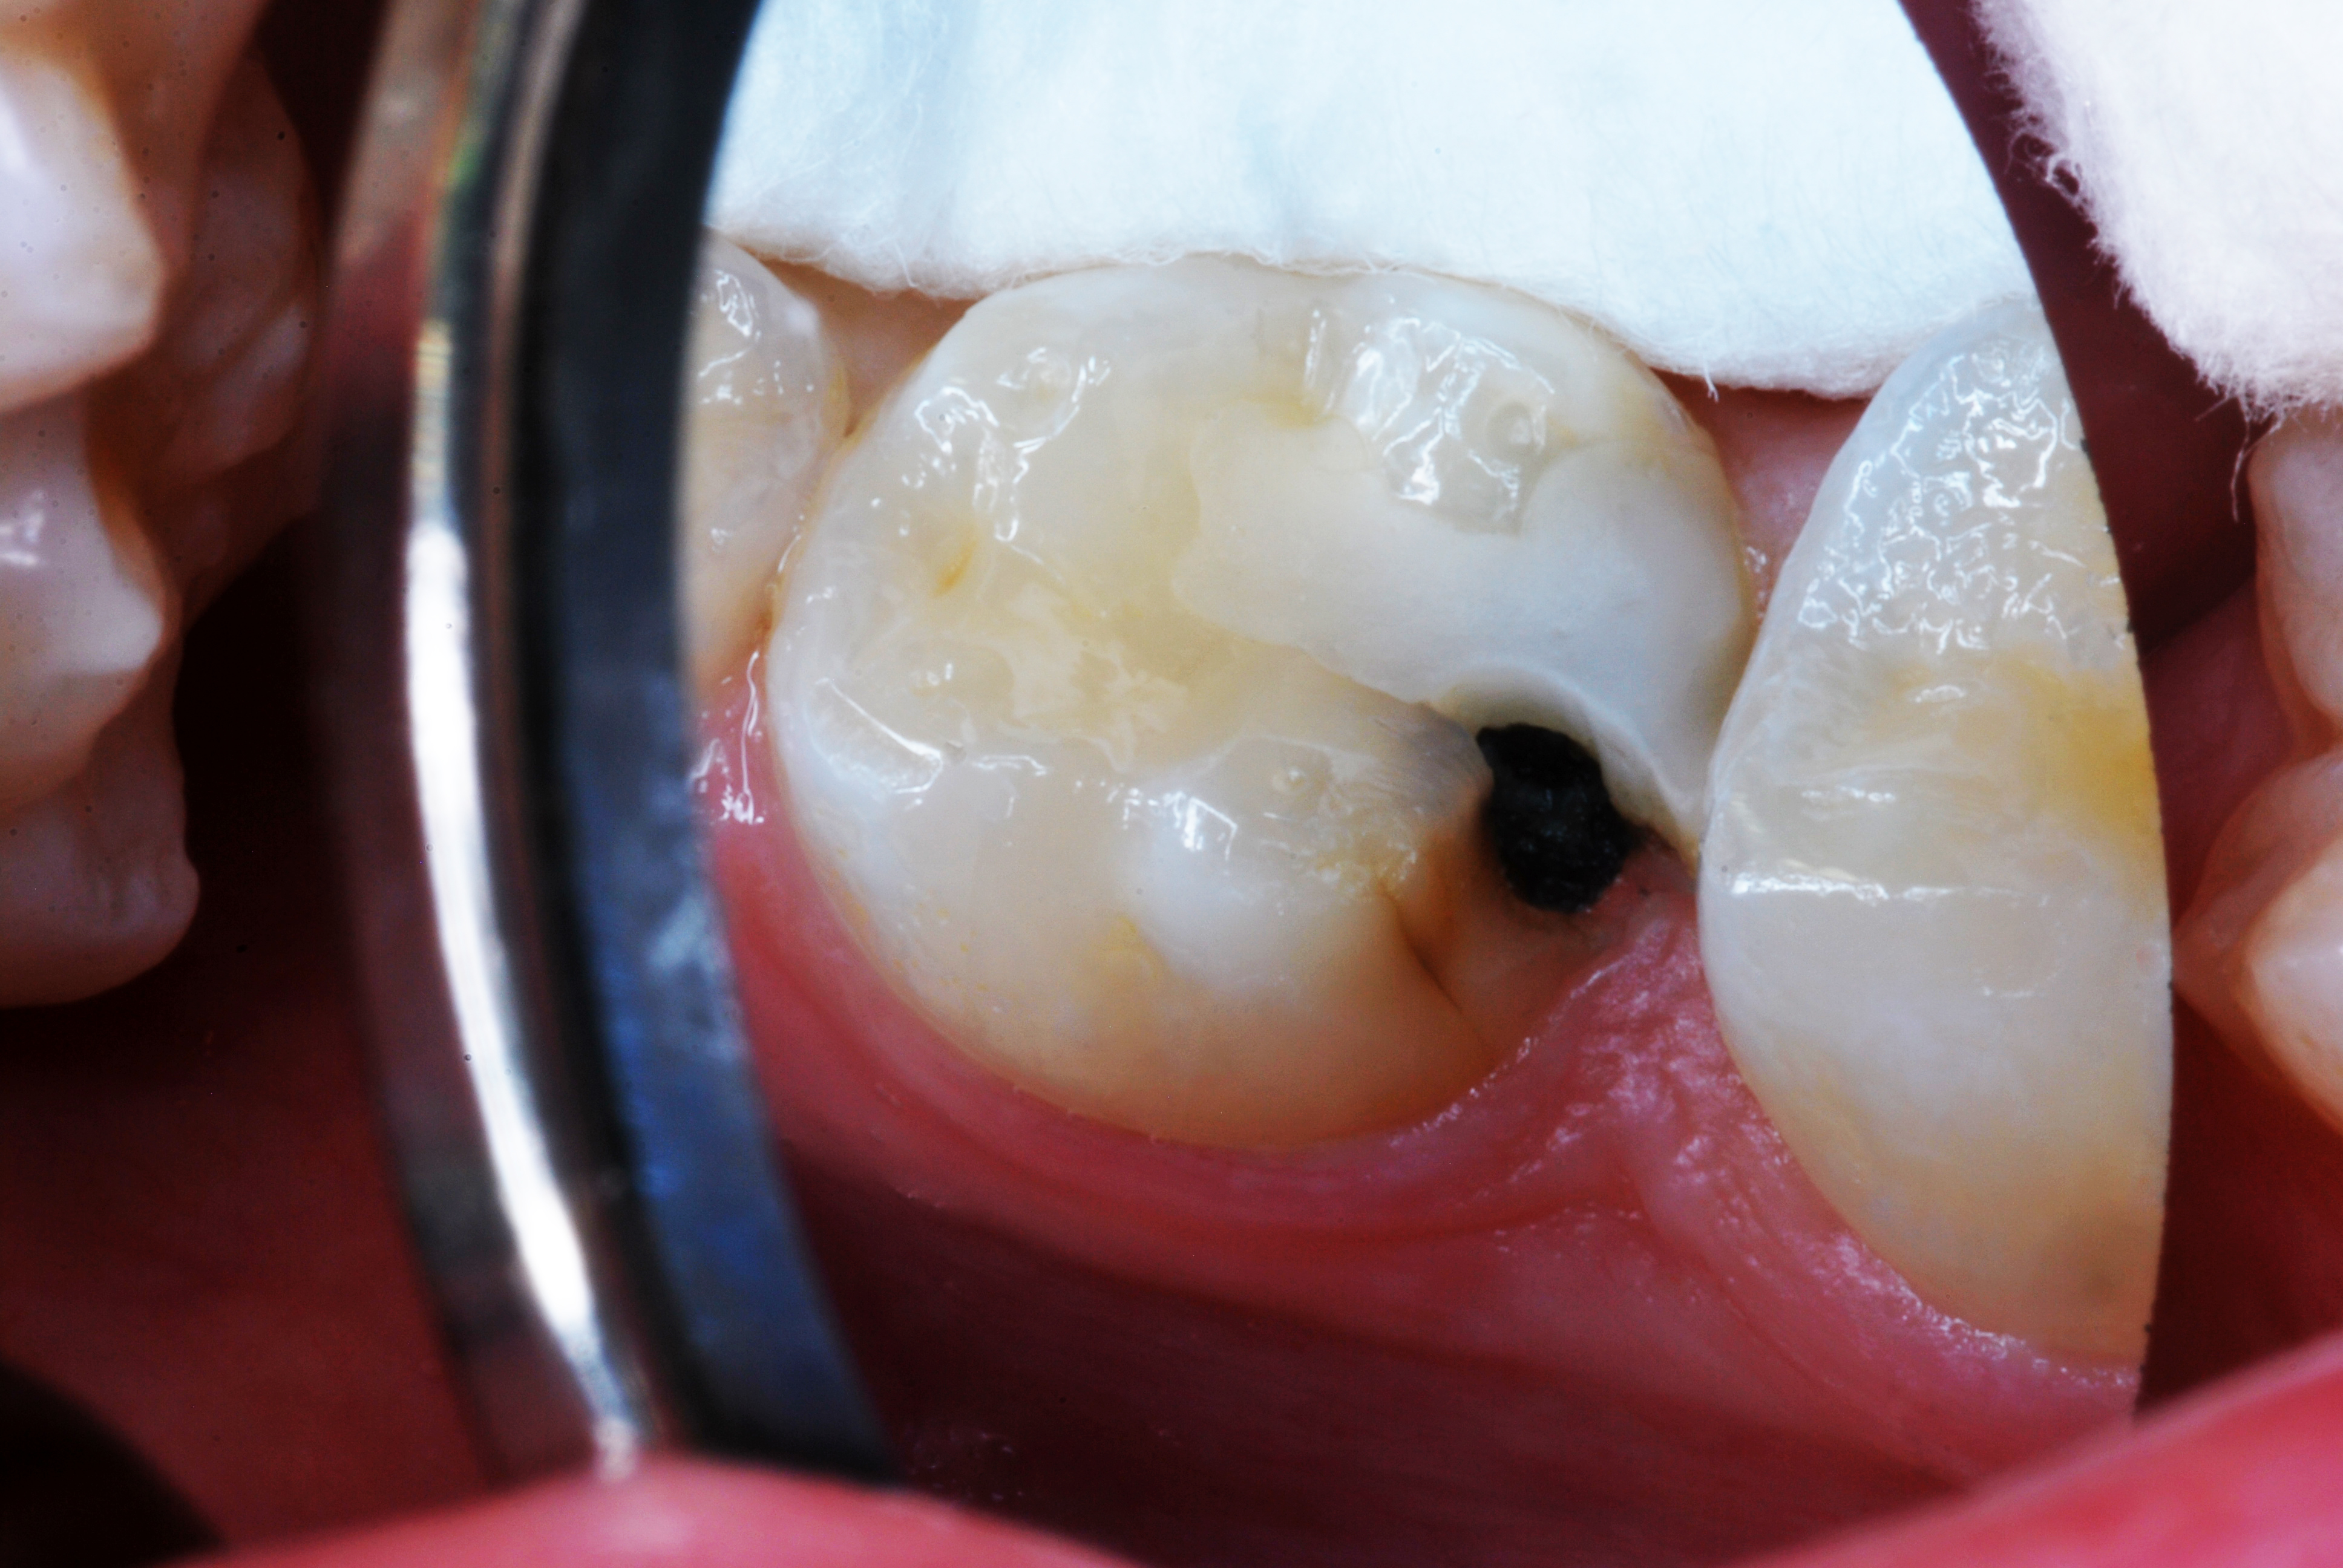

(4.) SDF treated molar in a 3-year-old patient, 4 months after application.

Figure 4